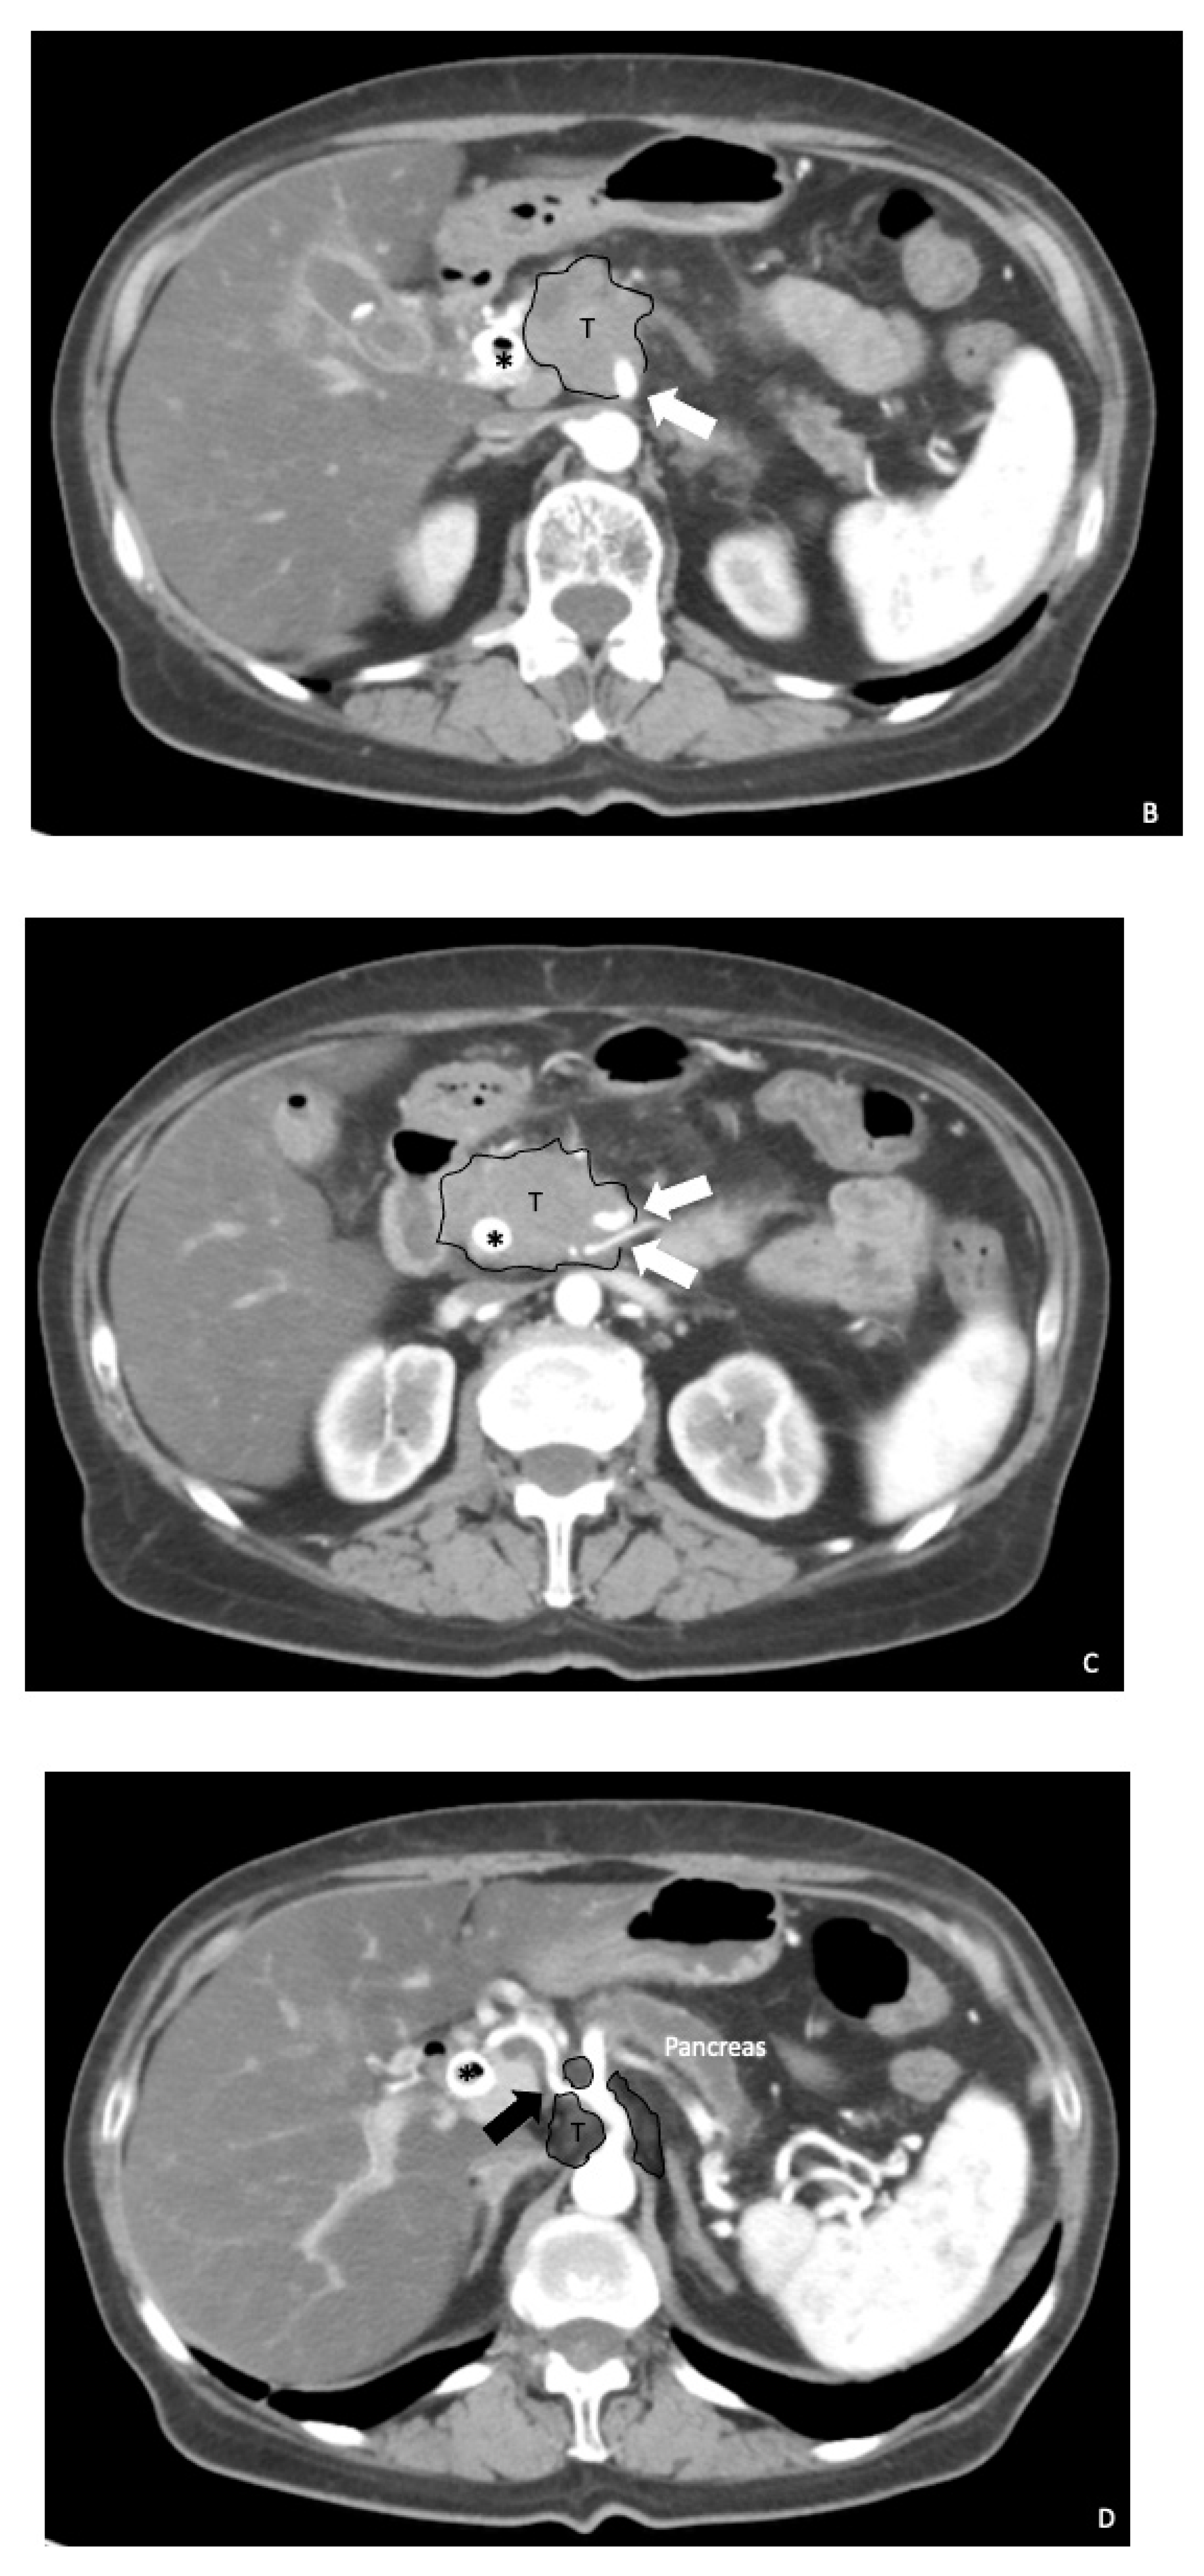

2. Preoperative Surgical Planning